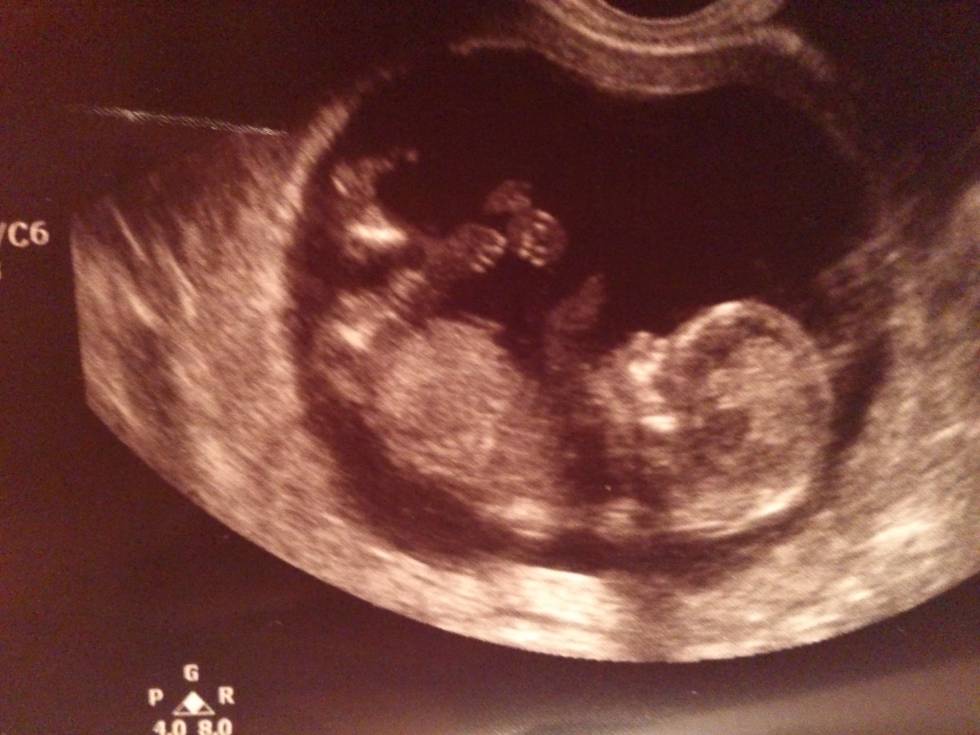

11+4

Na usg wiercił się niesamowicie, chyba zabiera mi całą energię bo ja chodzę półprzytomna ! No ale nie mam mu tego za złe ;) ;)